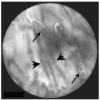

Results: Earlier published criteria were used to evaluate possible malignancy in the confocal images obtained in the 14 patients. None of the individual criteria were found to be specific enough for malignancy, but a normal-appearing reticular pattern without other putative markers of malignancy was observed in all normal patients. Multiphoton reconstructions of intact rat bile ducts revealed that the reticular pattern seen in normal tissue was in the same focal plane but was smaller than blood vessels. Special stains identified the smaller structures in this network as lymphatics.

Conclusions: Our limited series suggests that a negative confocal imaging study of the biliary tree can be used to rule out carcinoma, but there are frequent false positives using individual earlier published criteria. An abnormal reticular network, which may reflect changes in lymphatics, was never seen in benign strictures. Better correlation with known histologic structures may lead to improved accuracy of diagnoses.